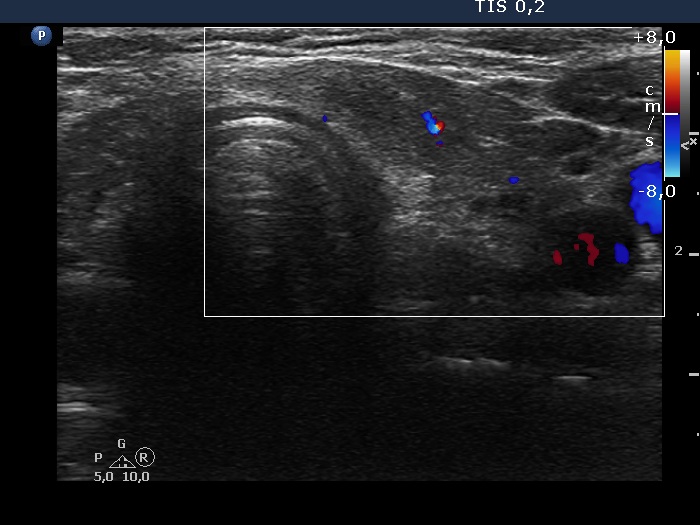

The shape of the nodule - case 2122 (ultrasonographic picture 11)

Left lobe, transverse scan, color Doppler mode. The vascularization is decreased.